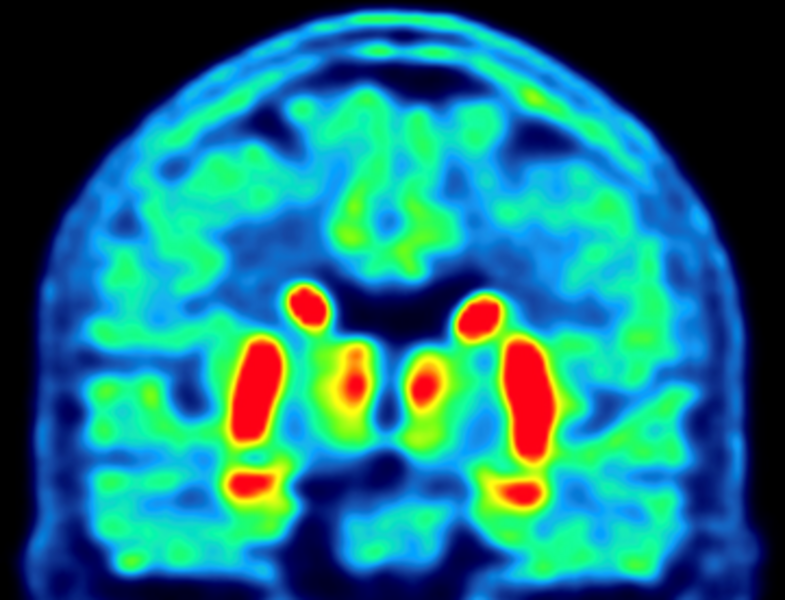

PET/CT scanning of the brain

Participants receive an injection with a small dose of the tracer [18F]PE2I. Subsequently, a PET/CT scan of the head is performed. The tracer measures the amount of functioning dopamine cells in the brain. The dopamine system is damaged in all patients with PD, but the symmetry and the progression of the damage might be different depending on the subtype of PD.

[18F]PE2I PET of the brain

Participants are injected with a small dose of [18F]PE2I. Thirty minutes later, a PET/CT of the head is performed. [18F]PE2I measures the dopamine system in the brain. The dopamine system is damaged in all patients with PD, but the degree of asymmetry and the progression of the damage might be different depending on the subtype of PD.